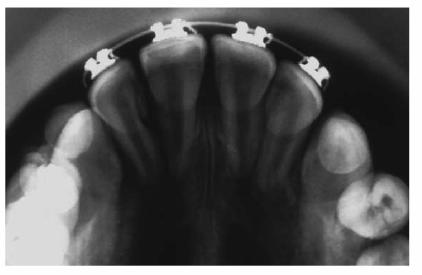

A male patient, 8 years, 3 months old.

PROBLEM: The patient presented with a supernumerary incisor and a double

tooth in place of the central upper left incisor (tooth #9) (Figures 27-11A and B). This anomaly manifests itself as a

structure resembling two teeth that have been joined together. In the anterior

region, the anomalous tooth usually has a groove on the buccal surface and a

notch in the incisal edge. Radiographs are necessary to determine if there is a

(fusion) union of the pulp chambers. Fusion exists when there is a joining of

two teeth by pulp and dentin. Two canals are usually present, as in this case.

Figure 27-11A and B: A supernumerary incisor and a double tooth in place of the central upper left incisor. Frontal and occlusal views.

TREATMENT: Both the supernumerary tooth and fused tooth were extracted (Figure 27-11C); also, the fixed orthodontic appliance was

applied to the maxillary arch to close the anterior diastema. Subsequently, the

incisal margin and the interproximal area of tooth #9 were restored to improve

esthetics (Figure 27-11D).

Figure 27-11C: Both the supernumerary tooth and fused tooth are extracted.

Figure 27-11D: An orthodontic appliance is applied to the maxillary arch to close the anterior diastema.

RESULT: The team work of several specialists created a good

morphic-functional recovery (Figures 27-11E and F) and an esthetic result that satisfied

the patient (Figures 27-11G and H).

Figure 27-11E and F: The morphic-functional recovery at the end of the orthodontic treatment.

Figure 27-11G and H: The final result showing the patient's smile at the end of the treatment.